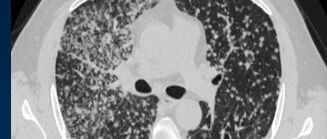

![]() 【间质性肺病影像诊断系列】肺间质解剖 肺部影像联盟 发布时间2026/01/09 22:18:29 | 2 | - | - | 75 | 更多 |